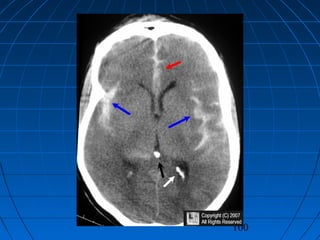

 FA: 56 yaşında erkek hastaFA: 56 yaşında erkek hasta

 Şiddetli başağrısıŞiddetli başağrısı

 GKS 14 (WFNS grade 2)GKS 14 (WFNS grade 2)

 Fisher grade IVFisher grade IV

CERRAHİCERRAHİ

 Sağ pterional trans-sylvian yaklaşımSağ pterional trans-sylvian yaklaşım

 MCA Anevrizması kliplendiMCA Anevrizması kliplendi